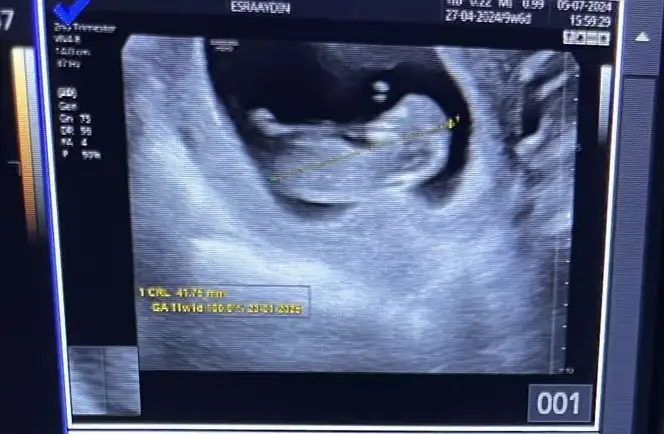

Bence kız Nub eğik açıBizede tahmin yapabilir misiniz acaba 10+4 üz![]()

Ben nubu göremedim doktor yan çekmemiş önden çekmiş ya onyüzden hiç yorumlayamadımBence kız Nub eğik açı![]()

Canım merhaba bende çok merak ediyorum sırf bu yüzden özele gidip ultrason aldım benımkıne de bakar mısınız rica etsem hepinizin yorumunu merak ediyorumKesinlikle kızzzz nub'u eğik